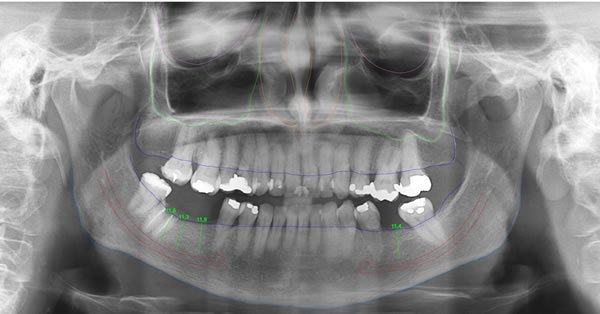

Panorâmica Digital